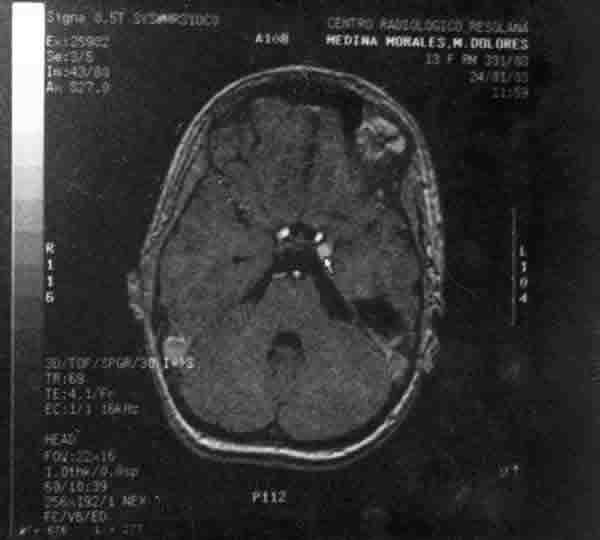

Solicitamos una angioRMC, informada como normal, y eco doppler de ambas órbitas en la que se nos informa de una mayor vascularización y mayor flujo demostrado con doppler color en la órbita izda. respecto de la derecha. La angio RMC con gadolinio (fig. 7) mostró unas imágenes que, sin ser concluyentes, sugerían la posibilidad de una fístula carótido-cavernosa izda. Al no estar plenamente convencidos de este diagnóstico decidimos, de acuerdo con el neurocirujano, practicar una arteriografía (fig. 8), la cual evidenció la existencia de un aneurisma en el territorio de la carótida izda. a la altura de la ACP. Dos días después se procedió a la embolización del aneurisma con espirales de platino (coils) (fig. 9).

Fig. 7.